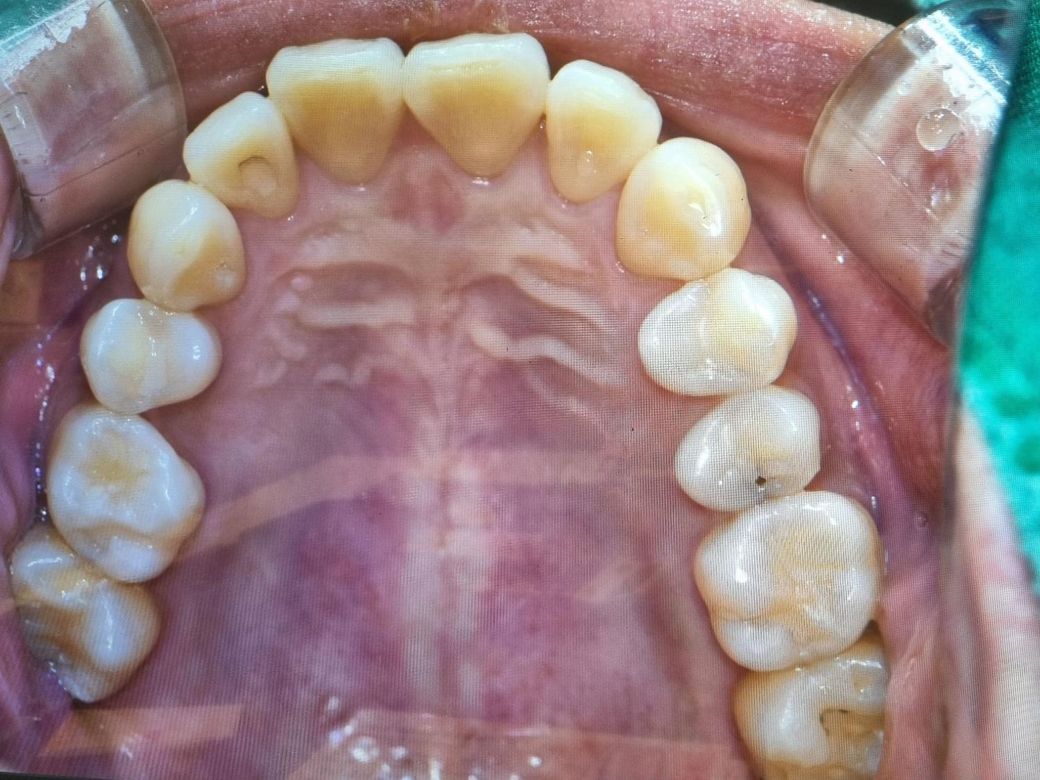

윗쪽 어금니 지아이로 치료가능한가요?

어금니는 깨지고 테두리에 충치생긴거고

3번째는 구멍생기고 그안에 충치생긴것같은데..

이건 지아이로 안되나요..?

현재 올려주는 어금니는 지아이로 치료할수 있는 정도는 아닙니다. 범위가 커서 신경치료 등이 필요해보입니다.

충치가 상당히 많이 진행된거 같습니다. 엑스레이를 찍어봐야 알겟지만 gi로는 치료하기가 어려울것같습니다.

사진으로 봤을 경우에는 인접면에 충치가 있는 것으로 보입니다. 인접면 충치의 경우 충치의 양이 많기 때문이 보철치료가 필요할수도 있습니다.

씹는힘이 가해지는 어금니 씹는면의 경우 설명들으신 것처럼 GI 재료로 하면 깨질 가능성도 있습니다. 다만 환자가 원한다면 GI로 하는데 파절 가능성에 대해서는 환자분이 동의해주셔야 합니다.

맨 끝 어금니는 충치가 아니라 착색일 가능성도 높아보이긴 합니다. 사진을 찍어봐야 알긴 하겠지만 원하신다면 GI로 해드리긴 합니다. 말씀하긴 것 처럼 금방 갈려나가거나 떨어질 수 있는데요. 비용이 걱정이라면 아말감으로 해주는 치과가 있는지 알아보셔도 되겠습니다.

세번째 구멍난 치아는 겉으로 보기에도 안쪽이 많이 썩은 것 처럼 보이긴 합니다. 신경치료와 크라운 가능성이 높긴한데 이런경우 GI로하면 이가 깨져나갈 가능성이 높아서 인레이나 신경치료 및 크라운 치료가 필요할 것으로 보입니다.